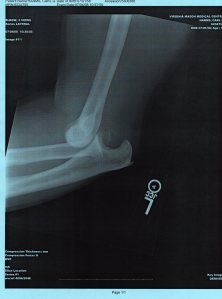

But the elbows we are dealing with today are those that are dislocated – another thing our family seems to do well.

Carl was playing in an All-Star baseball game, at first base, in the bottom of the first, and caught the ball and the base runner all at the same time. Then we got to see the very nice firefighters, ambulance drivers, nurses, x-ray technicians, doctors and casters. We also got to the Mariner’s game by the 2nd inning to see them win. We don’t know who won the all-star game. 3-6 weeks in a cast is the estimate. Will find out more after meeting with the orthopedist next week. Left arm – but he is left-handed. He is already trying to see how much he can do wrong-handed. A few dishes and he is now trying writing right-handed.